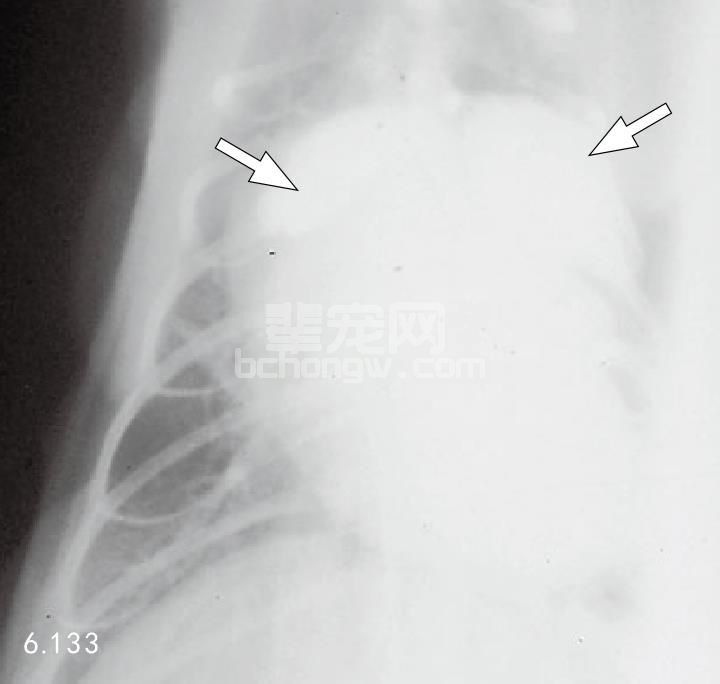

X线片 因为肥大变化是向心的,胸部X线片可能并不明显(图6.130)。由于左、右心房肥大,在腹背位 投影时心脏显现“瓦伦汀(valentine)”形状(图6.131)。这种情形可能发展到左侧或全心肌扩大症。左侧心 衰的猫常常有肺充血和组织间隙性的(而不是肺泡)肺水肿(图6.132和图6.133)。

图6.132和图6.133 患HCM的18月龄的缅甸猫侧位(图6.132)及腹背位(图6.133)对比心血管造 影,显示左心房和右心房肥大(箭头所指)。